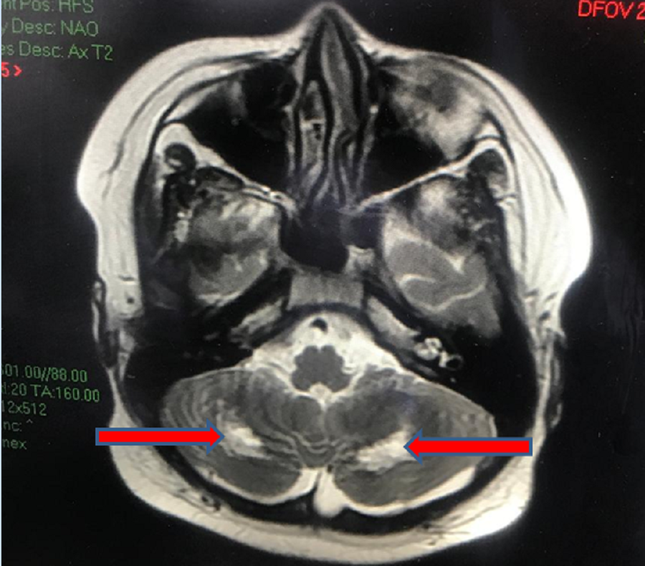

MRI não cho thấy tổn thương chất trắng vùng tiểu não 2 bên gây hiện rối loạn phối hợp vận động (ảnh: BV cung cấp)

“Điều trị gần 2 tuần tình trạng sức khỏe của trẻ từng bước bình phục, các chỉ số viêm cải thiện, xét nghiệm PCR SARS-CoV-2 cho kết quả âm tính. Tuy nhiên đến tuần thứ 3 bệnh nhi bất ngờ bị sốt lại kèm theo các biểu hiện đỏ mắt, đỏ da, rối loạn phối hợp vận động, đi lại loạng choạng, than nhức đầu. Các bác sĩ tiến hành xét nghiệm thì phát hiện phản ứng viêm trong máu bệnh nhi tăng cao. Kết quả MRI não ghi nhận tổn thương đồi thị hai bên, tổn thương chất trắng của tiểu não” – BS Nguyễn Minh Tiến, nói.